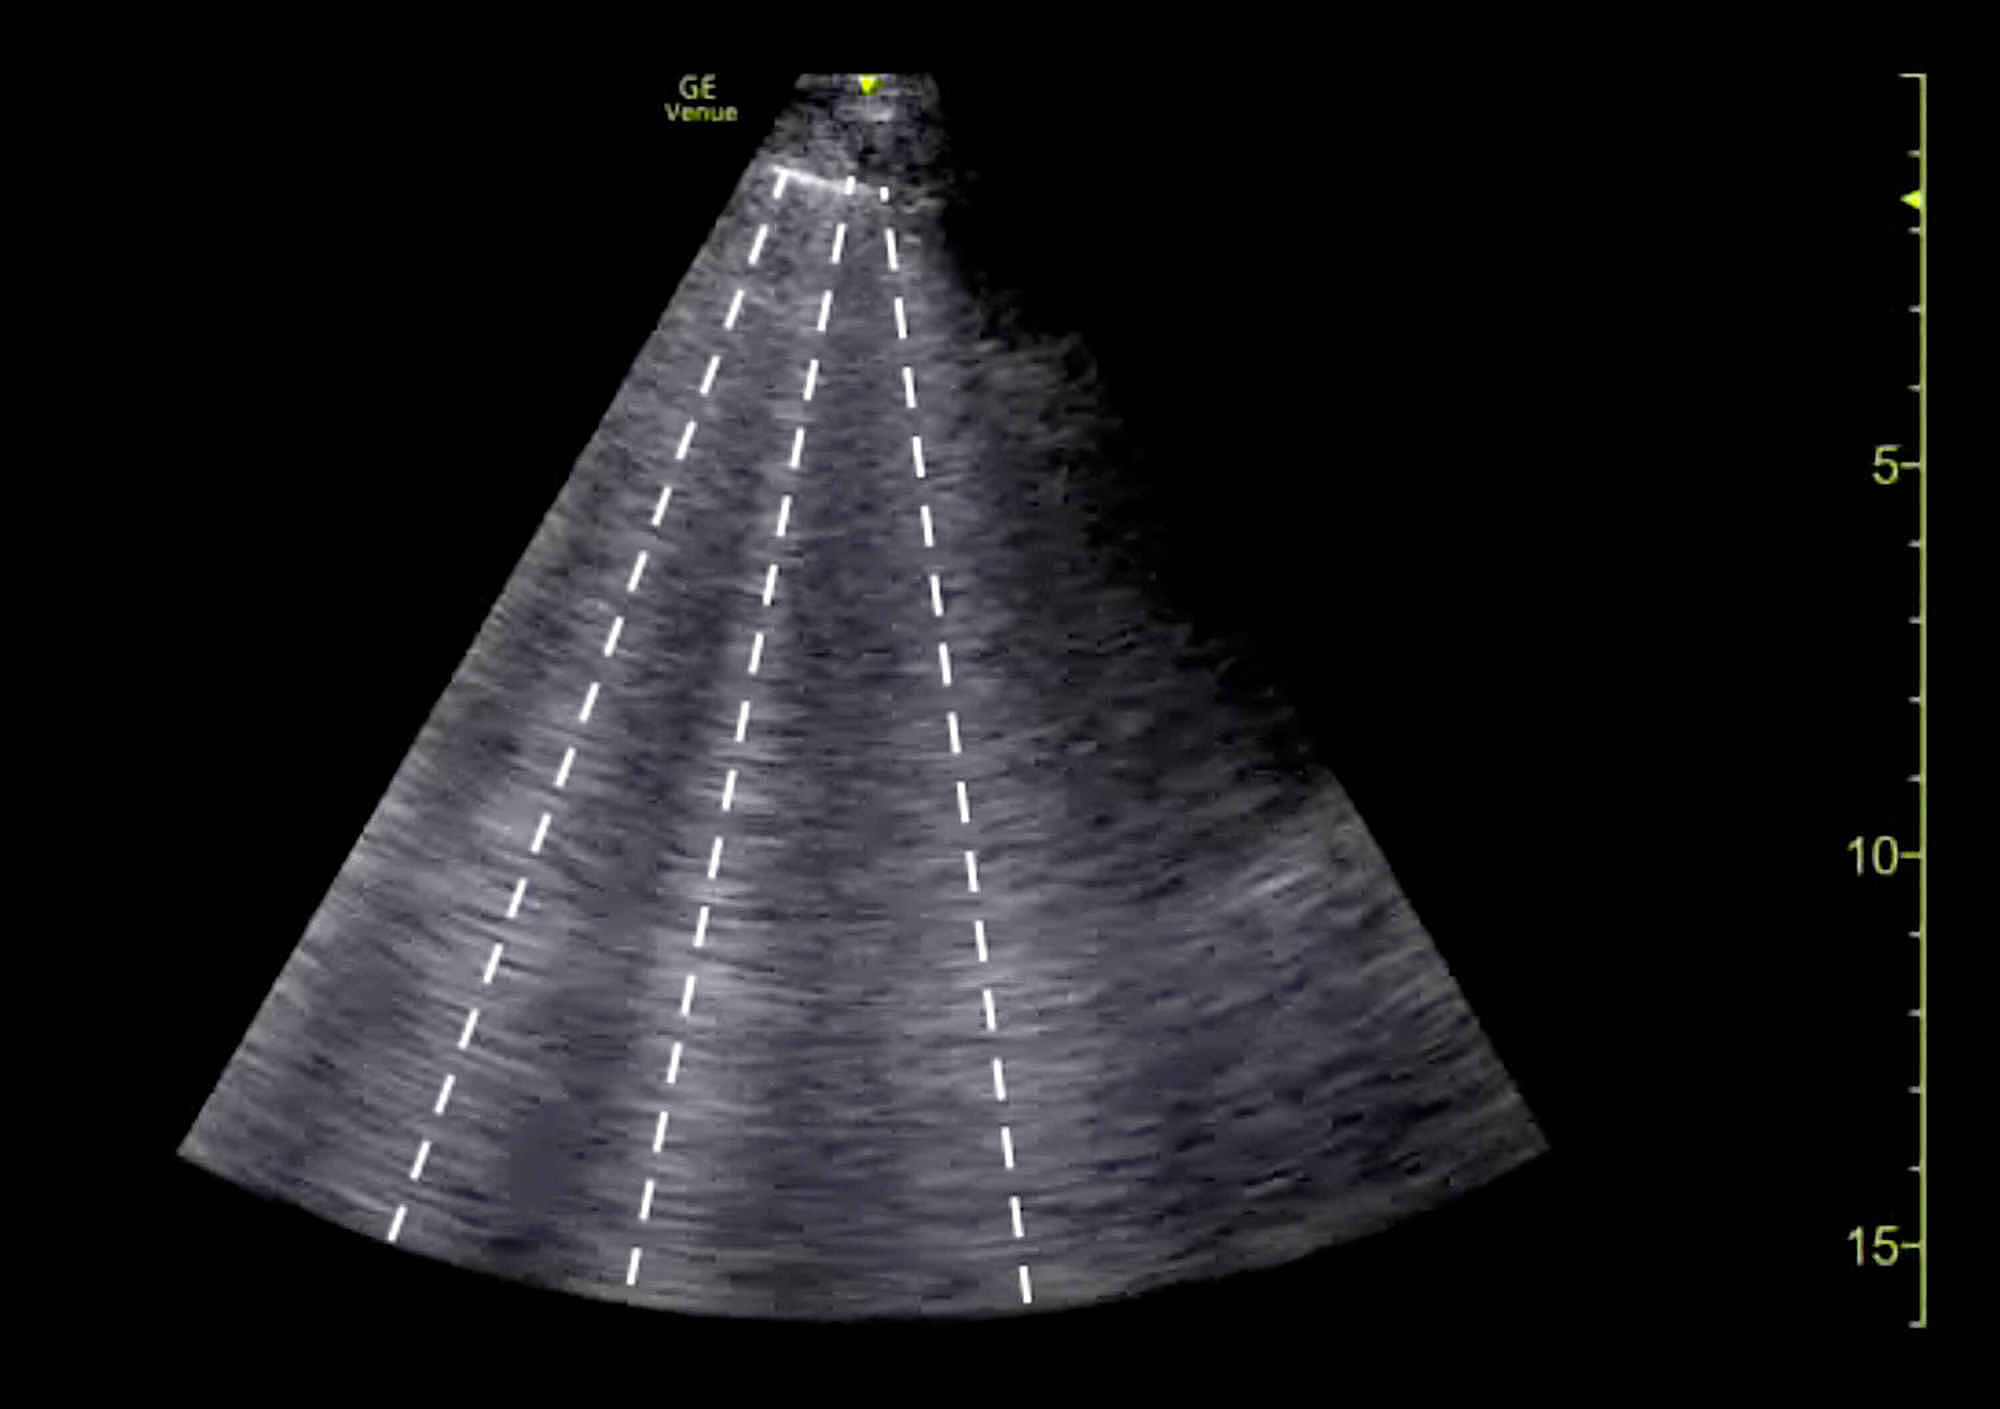

The clinical history was also concerning for an undiagnosed cardiomyopathy, particularly given the heart murmur appreciated on examination and his stated history of MVP for which the patient had never sought outpatient cardiology follow-up. Bedside LUS and FOCUS were then performed by emergency medicine resident physicians. LUS was notable for the presence of a diffuse B-line profile consistent with pulmonary edema (Figure 1). FOCUS was unremarkable for evidence of pericardial effusion, signs of right heart strain, or decreased LV contractility. However, FOCUS revealed a dilated left atrium (LA) and a suspected posterior FML, with the posterior MV leaflet seen protruding into the LA (Figures 2, 3; Videos 1, 2).